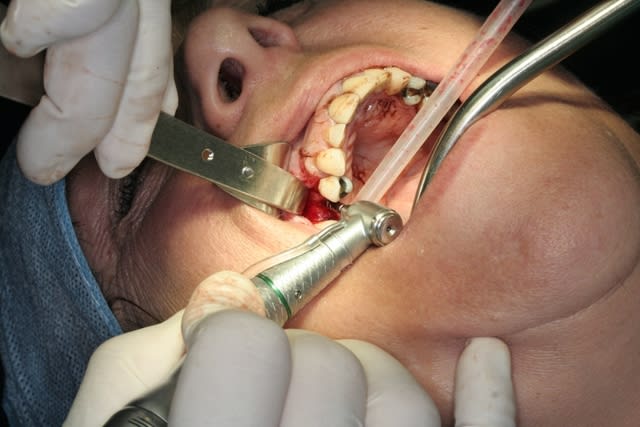

cette petite patiente ne veux pas d'ODF...mais ne veux pas rester sans dent...d'où cette intervention...avec la pose d'1 implant, avec expansion à l'aide de mon kit MIS... et mise en vitrine immédiate...

intervention totale flapless...y devrais pas trop y avoir de suites op...;-))

pour le flapless secteur anterieur il faut etre "prudent avec la concavité vestibulaire, il m'arrive de me faire avoir.

il est certain qu'avec les expanseurs sur le CA, tout va mieux, le patient y compris.